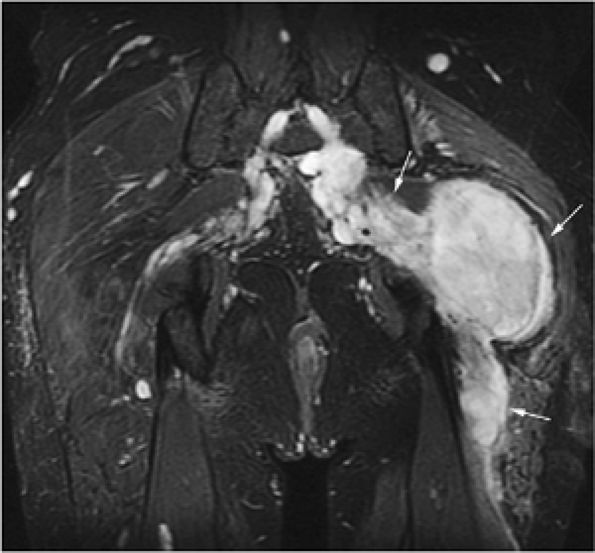

![]() |

FIGURE 14-5 ● FDG-PET in the evaluation of patients with sarcomas. Whole-body FDG-PET scan (A) and corresponding axial image (B) in a patient with neurofibromatosis type 1 demonstrates a region of intense FDG uptake in the right buttock area (arrow), which was found to represent a malignant peripheral nerve sheath tumor arising in a neurofibroma. (C and D) Images from a whole-body FDG PET scan in a patient with osteosarcoma show intense FDG uptake in the proximal tibia (D) in the area of the tumor (arrow). Images of the chest and abdomen demonstrate no evidence of metastatic disease. A marker was placed over the left chest wall (C) (arrowhead). (E) Coronal, axial, and sagittal images of a whole-body FDG-PET scan in a patient with osteosarcoma of the right femur. The patient underwent resection of the right femur and total knee arthroplasty. MR images and CT scans were deemed inadequate for tumor evaluation because of metallic artifact. FDG-PET scan shows a cold defect in the region of the right knee arthroplasty (arrows) and no increased FDG uptake in the area of the right femur and knee.